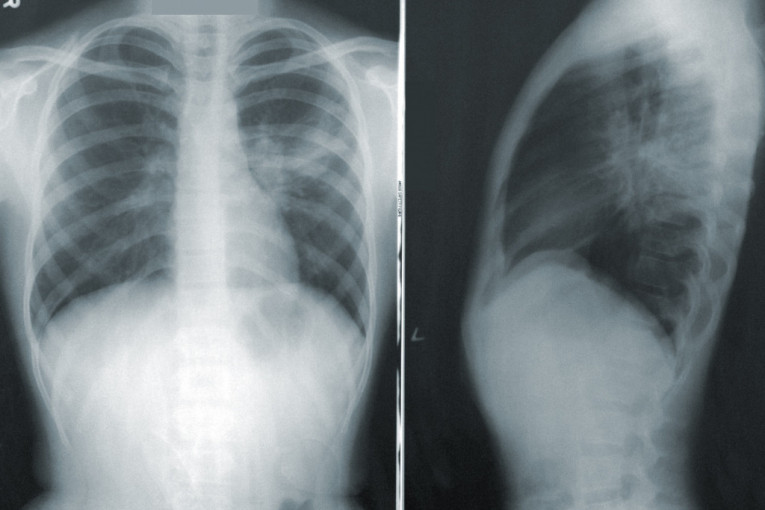

Lekari ističu da karcinom pluća uzrokuje oticanje lica i vrata ukoliko tumor pritiska venu između srca i glave. Taj simptom se naziva sindrom gornje šuplje vene ili opstrukcija vena cava superior.

Gornja šuplja vena vodi krv od glave i ruku ka srcu. Ona prolazi pored gornjeg dela desnog plućnog krila i limfnih žlezda. Svi tumori koji se nađu na ovom delu mogu da blokiraju normalan protok krvi.

Gornju šuplju venu mogu da pritisnu i karcinom dojke, limfom, ali i rak tiroide ili timusne žlezde.